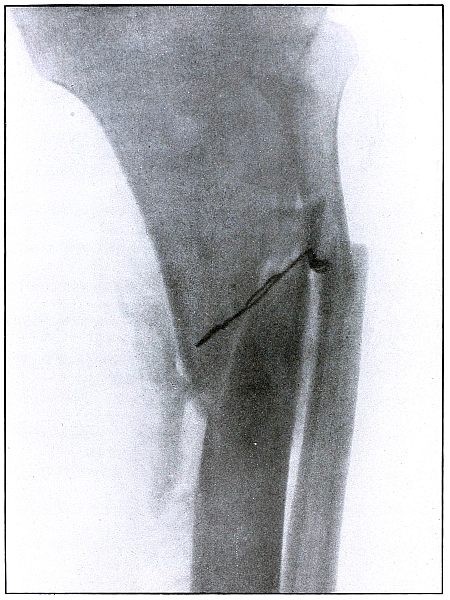

Gunshot fracture, tibia and fibula |

130 |

| 61. |

Gunshot fracture, tibia and fibula |